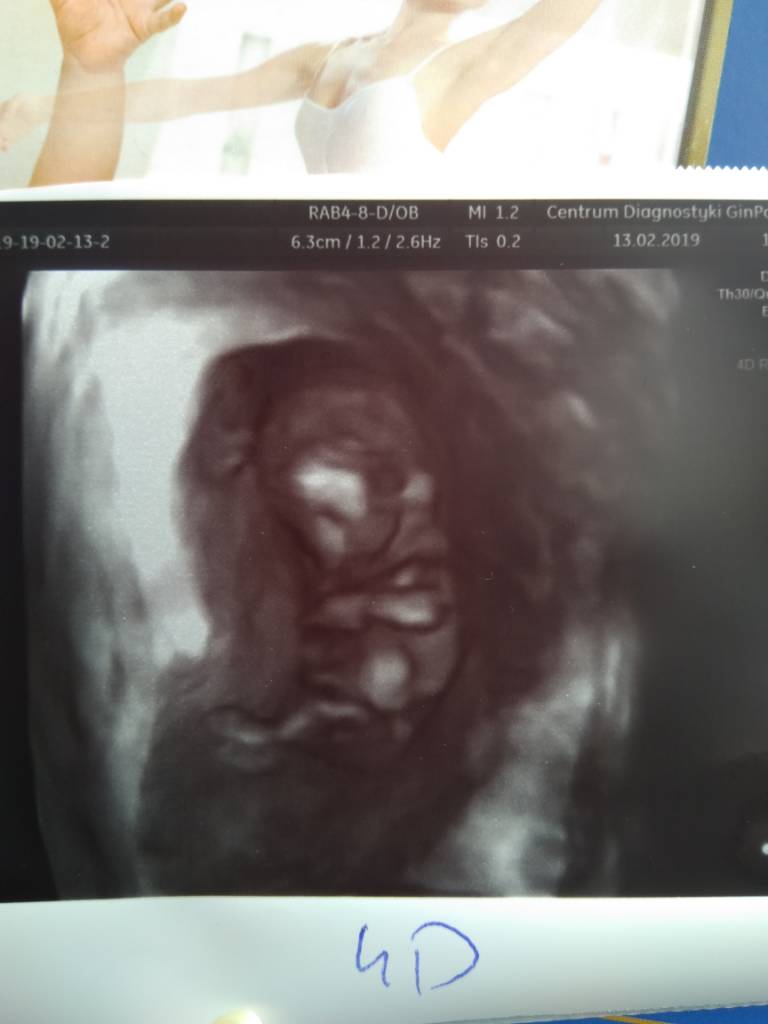

IMG_20190213_143254.jpeg